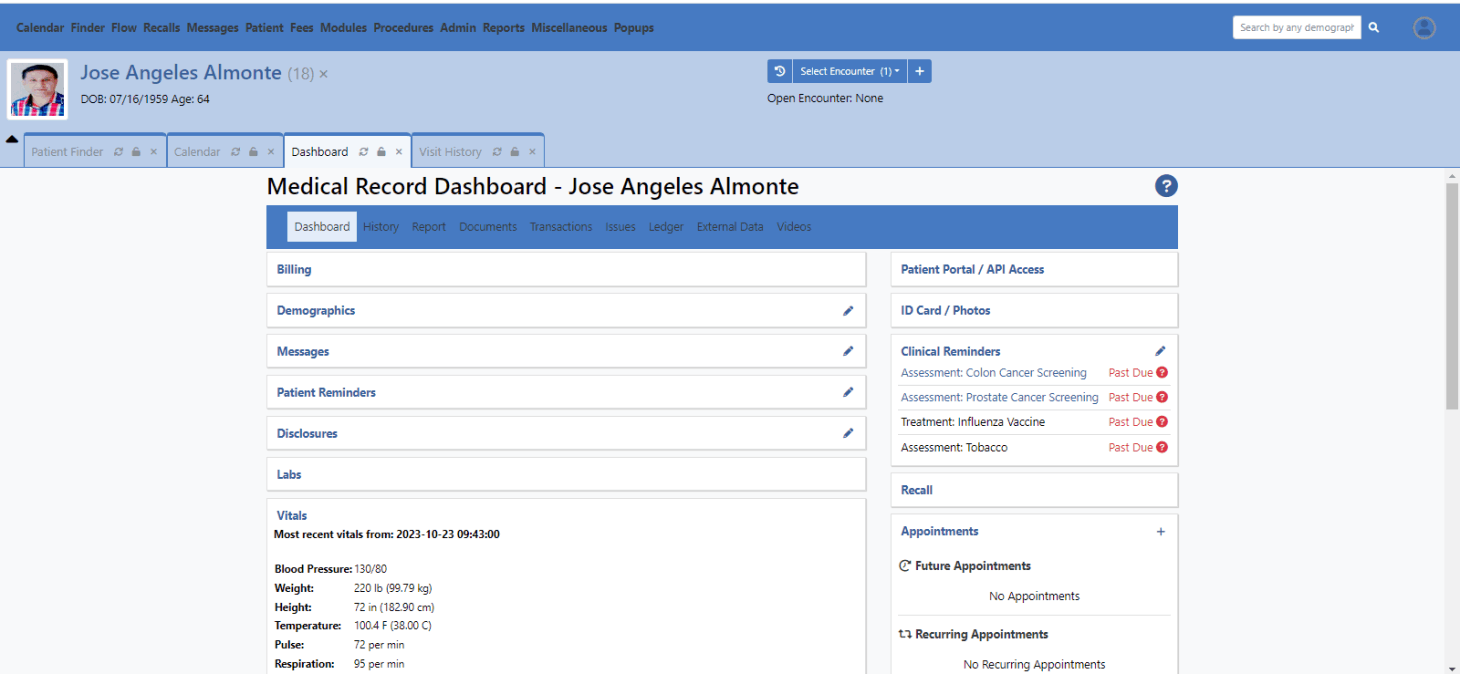

openEMR ( emr / ehr software ) :

OpenEMR is open-source ONC certified and fully HIPAA compliant, highly customizable Electronic Health Record (EHR/EMR) system that offers variety of features for medical practices.

Core Features :

Patient Management, Scheduling, Billing and Insurance Claims, e-Prescriptions, Reporting, Medical Coding, Dedicated Provider and Patient Portals.

Open-source benefits :

Felixibility, Customization, Full Data Ownership, and strong support community.

Additional features :

Multilingual support, Secure internal messaging, and ready built-in standard HL7 and FHIR APIs for connecting with third-party applications.

Specialities

- Deployment.

- Branding.

- Customization.

- Multi-Tenant EMR.

- HIPAA Compliance.